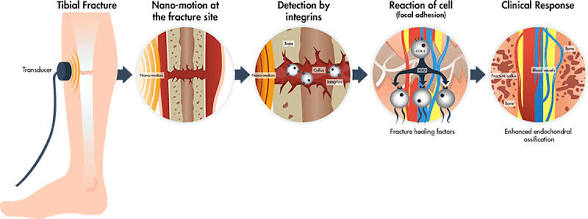

One area of interest in improving bone healing is Low-Intensity Pulsed Ultrasound (LIPUS). Research has shown that LIPUS can stimulate periosteal apposition, which is the formation of new bone along the outer surface of existing bone. This process is important not only for healing but also for changing the thickness and shape of bones.

Periosteal apposition plays a key role in how bones grow outward. Unlike lengthwise growth, which mainly happens during development, this type of growth affects the external structure of the bone. Because of this, it is relevant when considering changes in bone appearance or structure.

However, LIPUS alone may not be as effective by itself. some research suggests that LIPUS could be more effective when combined with other methods, such as drugs that increase bone-forming activity or support bone growth at a cellular level.

( examples would be Anabolic agents such as; Romosozumab , Teriparitide, and Abaloparitide, directly stimulate bone formation by increasing osteoblast activity or enhancing bone-building signaling pathways. When used alongside LIPUS, these agents may amplify localized bone growth by supplying more active bone-forming cells to the stimulated area. Similarly, systemic hormones such as GH and igf-1 further support this process by creating a more anabolic internal environment, potentially intensifying the response to mechanical stimulation.

In conclusion, LIPUS is a useful tool for supporting bone healing, particularly by promoting new bone formation on the outer surface. However, on its own, it is unlikely to cause significant changes in bone structure. Future advancements will likely depend on combining different treatments to better stimulate bone growt.

One area of interest in improving bone healing is Low-Intensity Pulsed Ultrasound (LIPUS). Research has shown that LIPUS can stimulate periosteal apposition, which is the formation of new bone along the outer surface of existing bone. This process is important not only for healing but also for changing the thickness and shape of bones.

Periosteal apposition plays a key role in how bones grow outward. Unlike lengthwise growth, which mainly happens during development, this type of growth affects the external structure of the bone. Because of this, it is relevant when considering changes in bone appearance or structure.

However, LIPUS alone may not be as effective by itself. some research suggests that LIPUS could be more effective when combined with other methods, such as drugs that increase bone-forming activity or support bone growth at a cellular level.

( examples would be Anabolic agents such as; Romosozumab , Teriparitide, and Abaloparitide, directly stimulate bone formation by increasing osteoblast activity or enhancing bone-building signaling pathways. When used alongside LIPUS, these agents may amplify localized bone growth by supplying more active bone-forming cells to the stimulated area. Similarly, systemic hormones such as GH and igf-1 further support this process by creating a more anabolic internal environment, potentially intensifying the response to mechanical stimulation.

In conclusion, LIPUS is a useful tool for supporting bone healing, particularly by promoting new bone formation on the outer surface. However, on its own, it is unlikely to cause significant changes in bone structure. Future advancements will likely depend on combining different treatments to better stimulate bone growt.